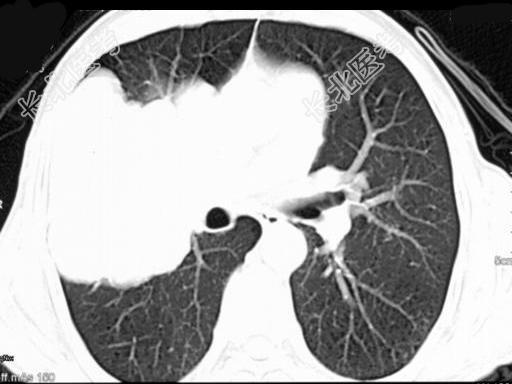

- 单项选择题50岁,男, 右侧胸痛、咳嗽、咯血3月,结合图像, 最可能的诊断是 ( )